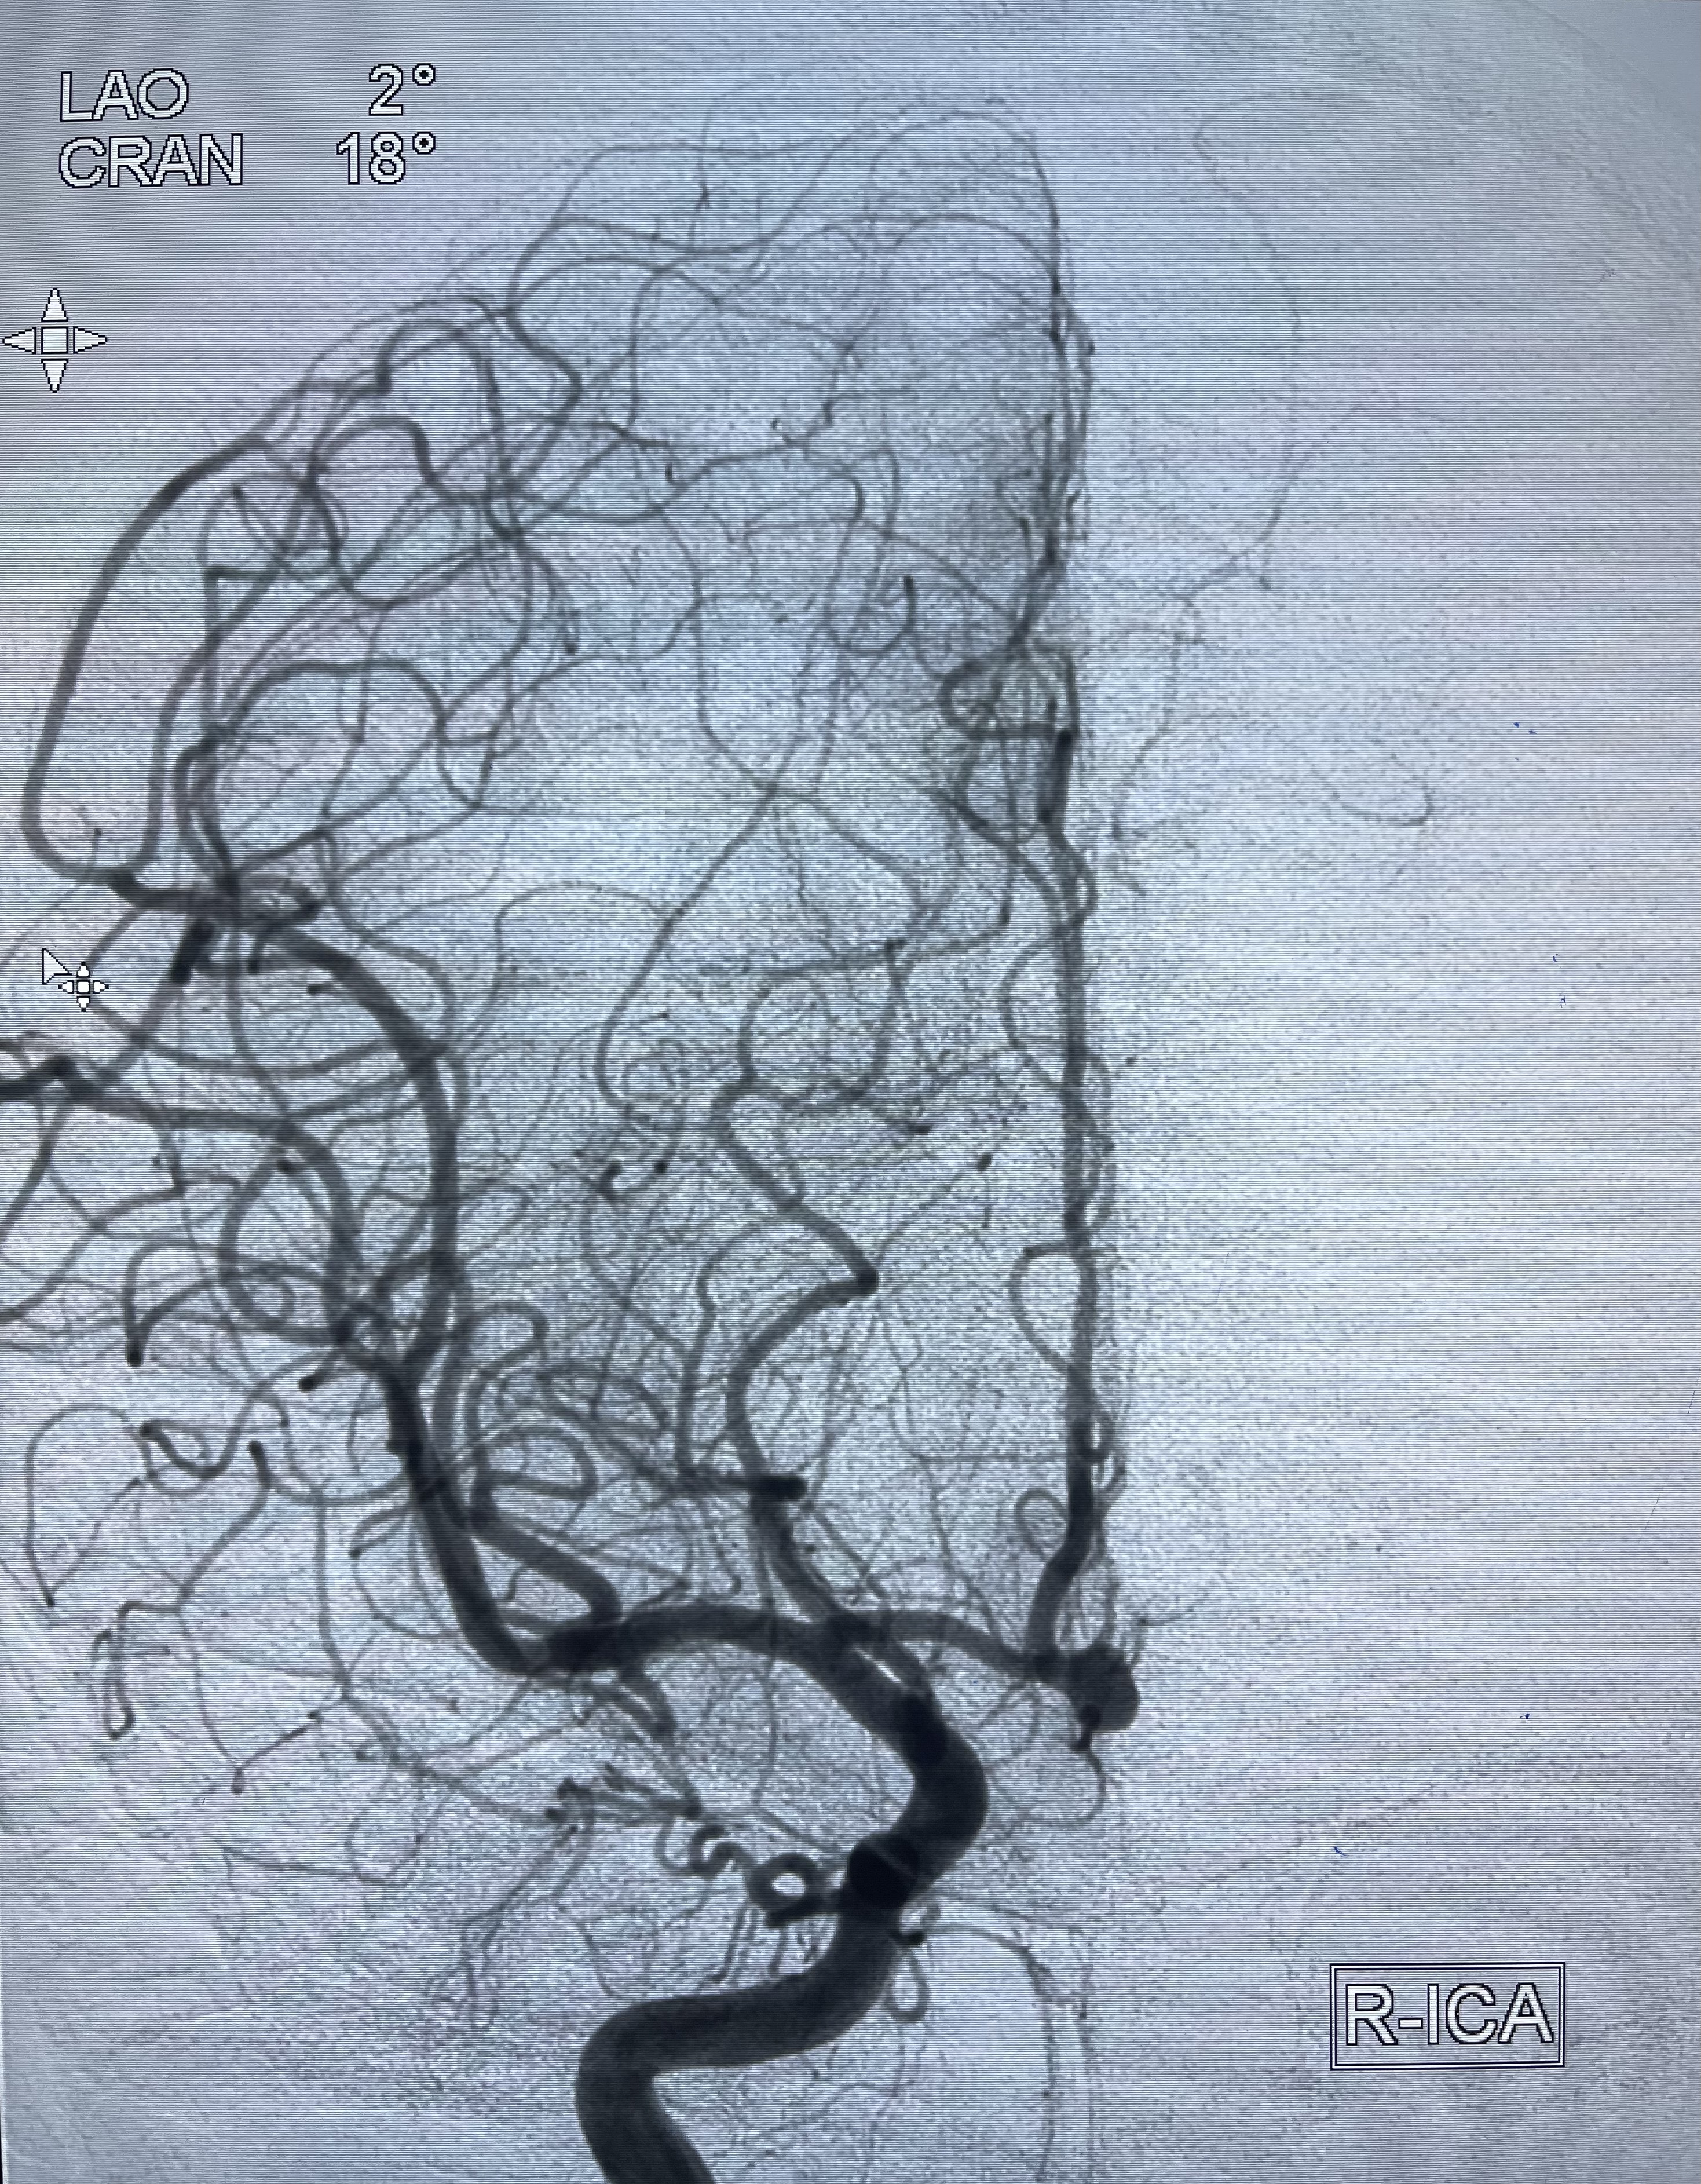

2021-01-07DSA

右侧前交通动脉瘤

箭头所示为左侧A2发出

工作角度显示瘤颈